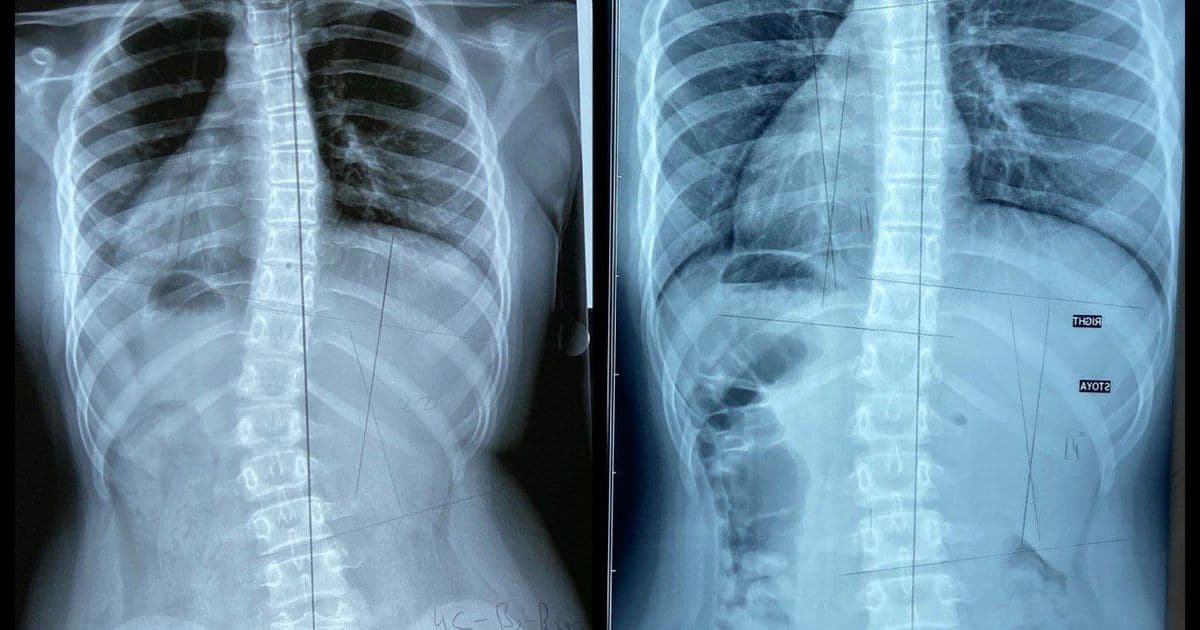

Сколиоз 19 Градусов Фото

Сколиоз 19 Градусов Фото 130 фото